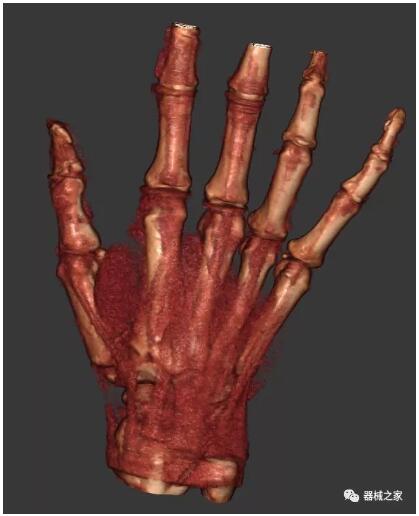

另外一款被稱為世界上最小的CT,它的重量僅300磅,不僅能夠掃查足部,還可以檢查膝蓋和上肢等。

這款CT使用非常方便,通過上下移動保持與患者的手臂或者雙腿齊平,掃描快速,僅需要30秒左右就可以完成掃查。

以上介紹的CT均來自國外同一家公司,這些CT均配置了可視化軟件,可以進行切片、3D重建以及大型CT附帶的所有典型的操作功能。

以下是這些“特立獨行”的CT所拍出來的圖像: